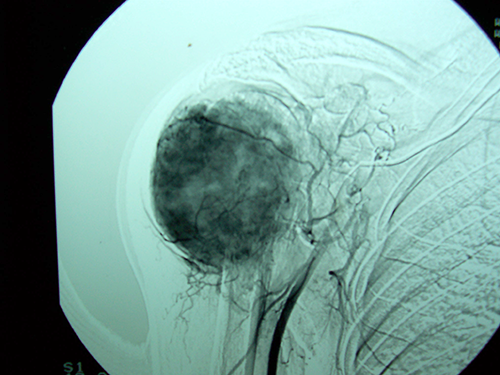

Case:6 Transfer of Scapula to Humerus

Orthopedic Oncology Doctor In Ahmedabad

Angio-2

Limb Reconstruction Doctor

Angiogram